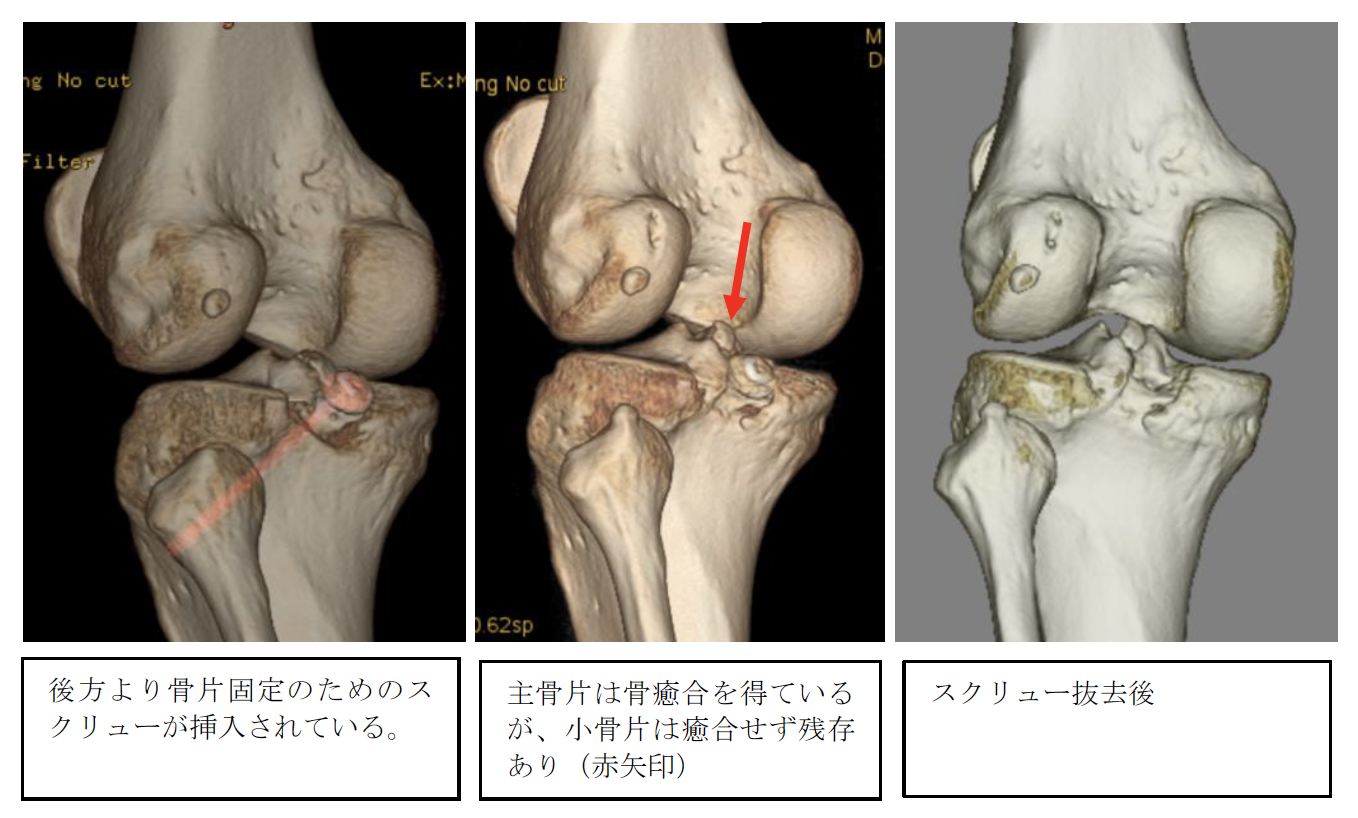

交通事故意見書(左後十字靭帯断付着部剥離骨折)本意見書の趣旨Purposs被害者は、左後十字靭帯断付着部剥離骨折により、可動域制限や疼痛に加え、筋力低 下も発生している。しかし、自賠責保険は、それらの症状を裏付ける画像所 […]

交通事故事例(左後十字靭帯断付着部剥離骨折)ご依頼経緯Request history被害者は左後十字靭帯断付着部剥離骨折により可動域制限や疼痛に加え筋力低下が発生しています。しかし、自賠責保険はそれらの症状を裏付ける画像 […]